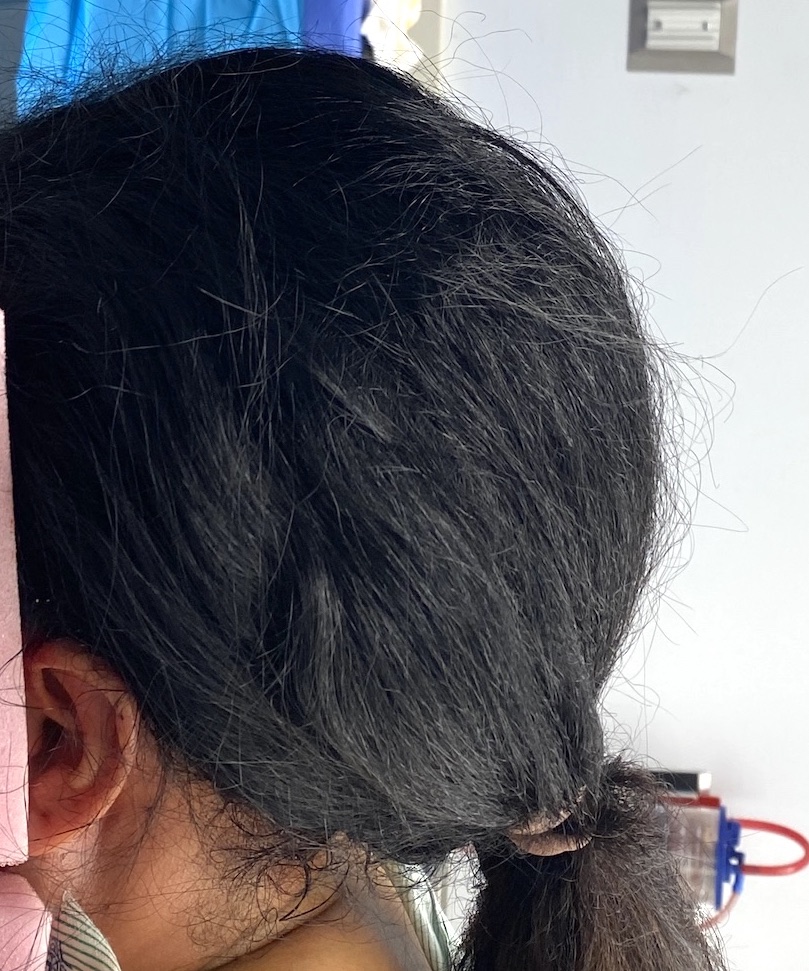

Desire to make her small head taller and wider.

Two stage skull augmentation using a first stage scalp expansion and a second stage custom skull implant for increased head height and shape.

Desire to make her small head taller and wider.

Two stage skull augmentation using a first stage scalp expansion and a second stage custom skull implant for increased head height and shape.